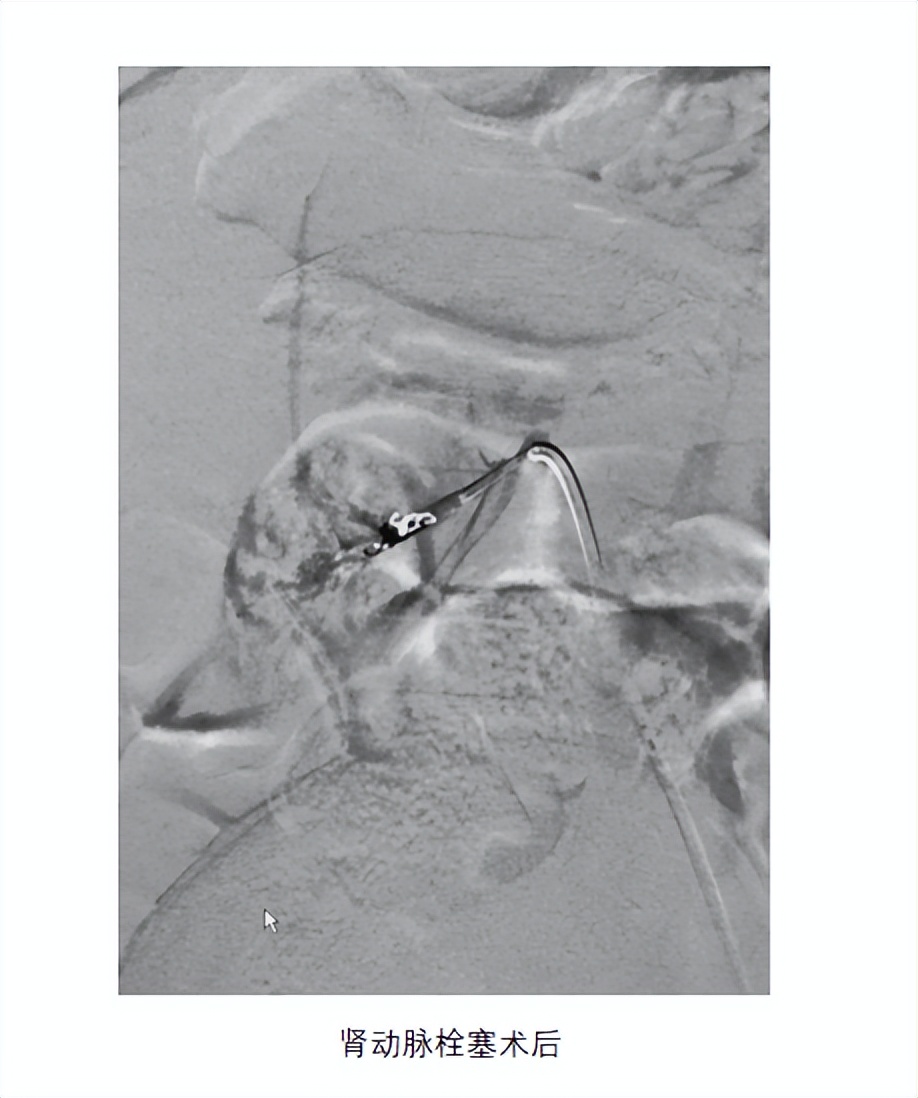

患儿做完手术前检查,无明显治疗禁忌,先行腹主动脉造影显示发自腹主动脉的异位肾动脉,微导管超选择入异位肾动脉,注入微球及弹簧圈行栓塞。栓塞后孩子无不适,第二天遗尿症状明显缓解。患儿妈妈的脸上也露出了久违的笑容。查完房后,办理出院。